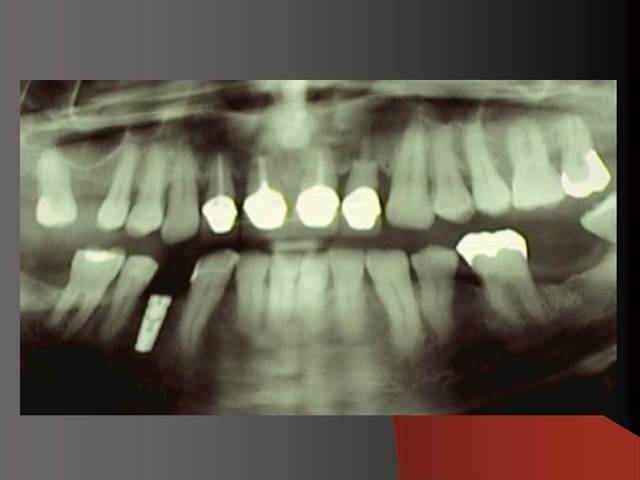

Photos d'un cas d'extraction implantation immédiate, stabilité primaire (de mémoire) assez élevée.. 60/70 N ..démontage du gingiva clips et du shuttle, pilier serré 40N, couronne procera

Merci pour le cas, bien fait. Belle présentation photo.

Le contour gingival est net, belle guérison, c'est à combien de semaine ?

Je vois un peu de ciment sur la radio finale, attention, c'est pas bien pour les tissus.

Oui je sais pour le ciment... j'utilise d'ailleur ce cas et cette radio dans une présentation pour mettre en garde sur le risque au moment du scellement de voir du ciment fuser sous la limite prothétique vers la col de l'implant..galère à éliminer...Personnellement je préfere plutot utiliser des piliers à usiner (maintenant disponibles voir shop online pour photos) au lieu des strandarts meme si il y a deux hauteurs/col implantaire en 1 et 3mm aujourd,hui disponibles..A l'époque de ce cas il n'y avait que les 1 mm et la limite est un "poil" trop profonde.

La pose de la couron nec'est faite 8 semaines apres l'extraction implantation immédiate, la particularité de ce systeme permet de ne pas démonter le shuttle ni la gingivaclip pour l'empreinte..je pense que ca aide bien à la qualité gingivale...radio controle ci jointe